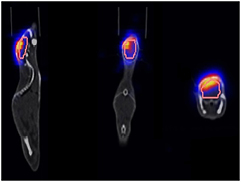

CT images (also used for attenuation and scatter correction of the PET data) were reconstructed with a pixel size of circa 0.605 mm and a slice thickness of 0.6 mm. The raw PET list mode data were reconstructed in two different ways: Static PET images were derived from averaging the activity values over the total measurement time. For dynamic PET images, the PET data sets were subdivided into shorter time frames over which the activity data were averaged. After testing a variety of configurations and algorithms, the time intervals (3 × 60 s, 4 × 180 s, 3 × 300 s) were chosen. All PET data were reconstructed using the filtered back projection (FBP) algorithm because of enhanced activity consistency between static and dynamic PET images (see section 2.3.1), with a pixel size of circa 1.06 mm and the same CT slice thickness of 0.6 mm. The resulting image data were saved in the digital imaging and communications in medicine (DICOM) format. Volumes of interest (VOI) containing the tumour and a large fraction of the brain were drawn by hand on the basis of the CT data using the scanner software syngo for quantitative evaluation. In this process, special care was taken to exclude regions close to the bone, resulting in VOI volumes of approximately 80 mm3 (figure 3).

Figure 3. Overlapped PET, VOI and CT data for an exemplary mouse.

Standard image High-resolution imageTo handle the image files, networks created in the software environment MeVisLab (MeVis Medical Solutions AG) were used, whose basic scaffold was developed at HIT (Unholtz et al 2011). The networks provided the possibility of overlapping and evaluating PET and CT images as well as the VOIs (figure 3). Using this software, the activity values of each voxel within the VOI were extracted from the PET images, summed and averaged. Hence, every time frame was assigned one value of activity, which was not dependent on location within the VOI, but only on the average activity of the VOI within the selected time frame. All evaluations of numerical data as described in section 2.3 were implemented using Matlab software (The MathWorks, Inc.). Additionally, the elemental composition of the tissue within the VOI was quantified by converting the Hounsfield units (HUs) of the DICOM CTs using a stoichiometric calibration table (Schneider et al 2000).